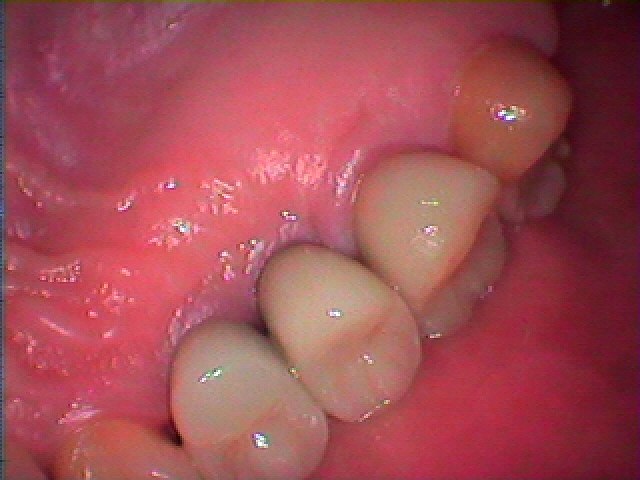

チタンのアバットメント、セラミッククラウンにて上部構造を作成しています。| |広島市安佐南区の歯科医院 チタンのアバットメント、セラミッククラウンにて上部構造を作成しています。 トップ お知らせ・ブログ チタンのアバットメント、セラミッククラウンにて上部構造を作成しています。 チタンのアバットメント、セラミッククラウンにて上部構造を作成しています。 Web診療予約 初めての方へ 選ばれ続ける理由 院内設備について 歯が痛いしみる一般歯科 歯がぐらぐらする歯周病 健康な歯を保ちたい予防歯科 子供の虫歯予防をしたい小児歯科 銀歯をセラミックに審美歯科 白い歯を目指しませんか?ホワイトニング 矯正専門医がいるので安心矯正歯科 抜けた歯を補いたいインプラント・入れ歯 医院案内 スタッフ紹介 メリィハウス歯科クリニックオフィシャルホームページ ラベンダー歯科クリニックオフィシャルホームページ お知らせ・ブログ ホーム 診療科目 一般歯科 歯周病治療 予防治療 小児歯科 審美治療 ホワイトニング 矯正歯科 入れ歯・インプラント マウスピース矯正 初めての方へ 院長・スタッフ 設備紹介 医院案内・アクセス メニューを閉じる